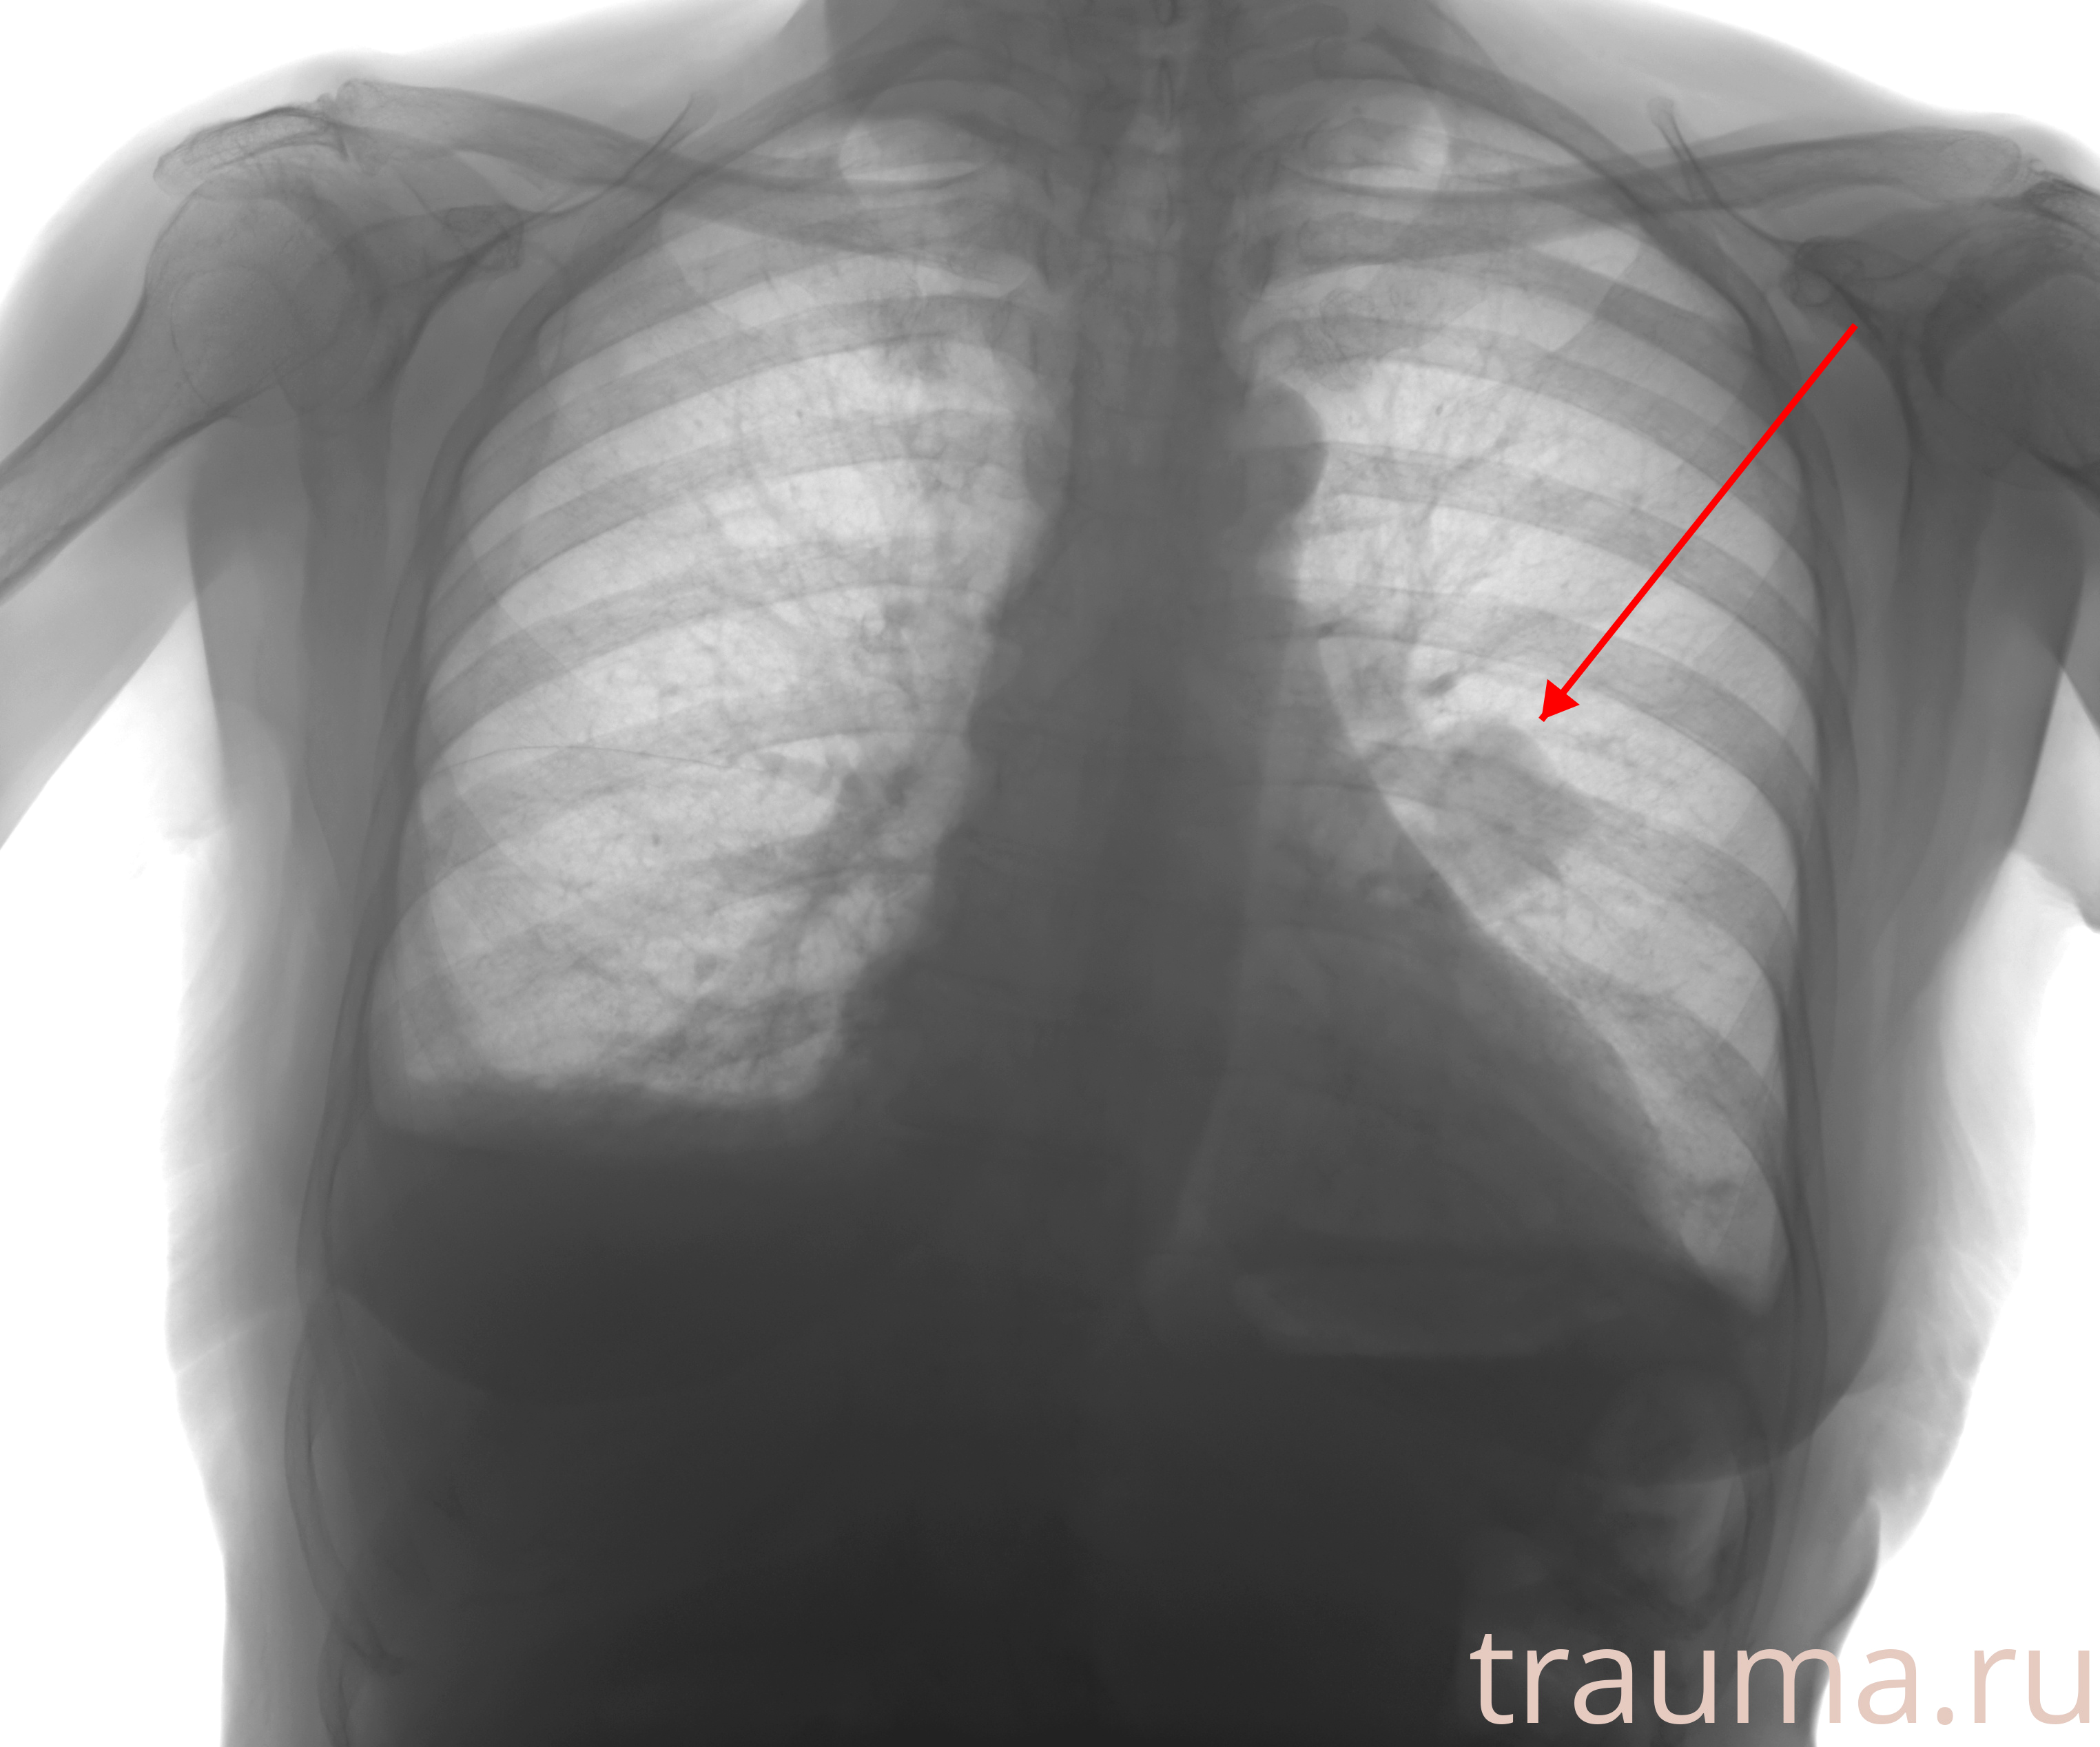

Рентгенограммы

Натуживание 26.12.2025 21:16:34

Рентген на дому: по вашему адресу приезжает врач-рентгенолог, травматолог-ортопед с мобильным рентгеновским аппаратом, проводит диагностику травмы или заболевания, делает необходимые рентгенограммы, дает рекомендации по дальнейшему лечению. Получить качественные снимки в домашних условиях возможно благодаря уникальной методике, разработанной МосРентген Центром для института  Склифосовского